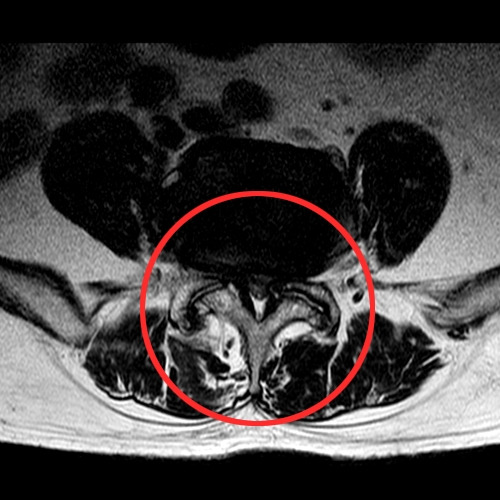

척추관이 좁아진 환자의 MRI

신경학적 파행이란 이미 퇴행성 변화로 인해 오랜 시간에 걸쳐 척추관이 좁아져 있기 때문에 환자가 걷게 되면 척추관에 체중이 실리면서 신경압박이 더욱 심해집니다. 신경학적 파행이 나타나면 신경이 눌리면서 다리가 저리거나 아파 걷지 못하는 증상이 척추관 협착증 환자들이 가장 많이 호소하는 증상이라고 할 수 있습니다. 신경학적 파행은 영상 의학 검사를 하기 전 신경학적 파행의 거리만으로도 척추관 협착증의 정도를 유추할 수 있습니다.